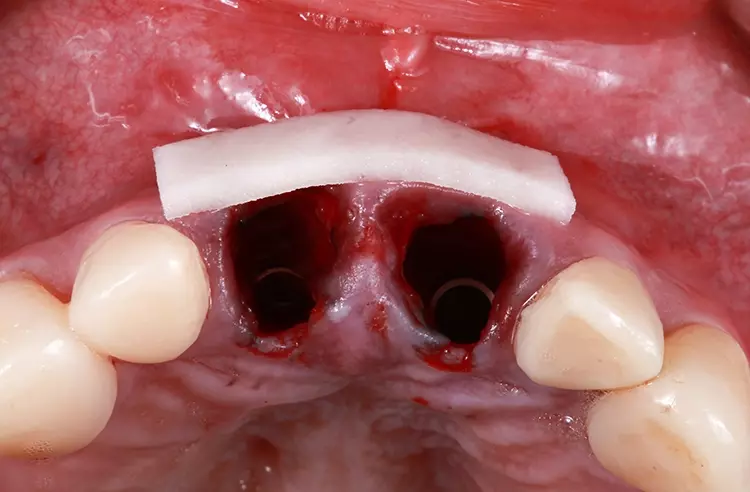

Die Bohrschablone wurde additiv aus speziellem 3D-Druckharz (Cosmos SG, Yller) auf einem Photon Mono 4K (Anycubic) hergestellt. Die Zähne wurden atraumatisch unter Erhaltung der Integrität der Gingiva und der Gingivaarchitektur extrahiert (Abb. 11).

Die Kronen für 11 und 21 wurden mit einer 5-Achs-Fräs- und Schleifmaschine (inLab MC X5; Dentsply Sirona) aus einer nanokeramischen Komposit CAD/CAM-Ronde (Grandio disc, A1, VOCO) gefräst und mit Bifix Hybrid Abutment (VOCO) auf einem Abutment aus Metall (Grand Morse, Neodent Titanium Base Neodent, Straumann) im Labor zementiert. Die Kronen wurden in ihrer endgültigen Position eingegliedert (Abb. 18). Jede Krone wurde mit direkten Komposit-Veneers modifiziert.

Basierend auf dem klinischen Befund einer Grad-3-Mobilität und den röntgenologischen und computertomografischen Befunden einer Wurzelresorption und postendodontischer periapikaler Granulome wurde entschieden, beide mittleren Schneidezähne zu extrahieren und durch Implantate zu ersetzen. Der Verlust der vertikalen Dimension der Okklusion und die fehlende anteriore Führung würden die sofort belasteten Implantate gefährden. Aus diesem Grund wurde die Stabilität der Okklusion vor dem chirurgischen Eingriff wiederhergestellt.

Die Nanohybrid-Komposite für Kronen und Veneers wurden aufgrund ihrer mechanischen Eigenschaften (ähnlich denen natürlicher Zähne), ihrer Farbstabilität und ihrer einfachen Reparatur und Charakterisierung im Mund des Patienten ausgewählt. Es wird erwartet, dass die Implantatkronen und entsprechenden Titanabutments über einen langen Zeitraum in Funktion bleiben können, ohne dass sie entfernt werden müssen, sodass der Implantathals sowie das Hart- und Weichgewebe keine signifikanten klinischen Veränderungen erfahren („one-abutment/one-time“-Konzept). Die Haltbarkeit des verwendeten Kompositmaterials und die Stabilität des periimplantären Gewebes sollten im Rahmen einer Langzeitbeobachtung dokumentiert werden.